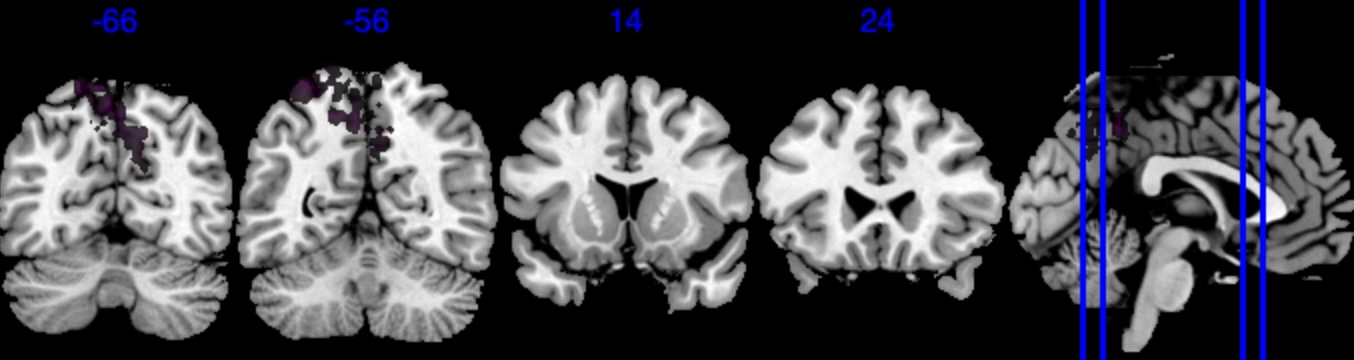

| Posterior inclusion probability (color range ) |

![]() |